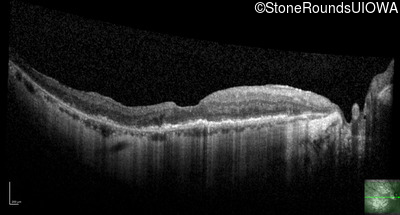

This 81 year old man began using a flashlight to read menus in his 40's. At age 75 his ophthalmologist noticed abnormal fundus findings and referred him to a retina specialist.

| Late Onset Retinal Dystrophy | C1QTNF5 | Ser163Arg AGC>AGA | AD |